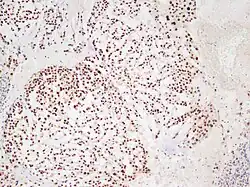

Micrograph showing a classical chordoma with its typical features. H&E stain.

Chordoma showing nuclear staining for brachyury using immunohistochemistry.

There are three histological variants of chordoma: conventional,[14] chondroid and dedifferentiated.

• The histological appearance of classical chordoma is of a lobulated tumor composed of groups of cells separated by fibrous septa. The cells have small round nuclei and abundant vacuolated cytoplasm, sometimes described as "physaliferous" because of their cytoplasmic vacuoles, and their resemblance to the physalis plant.